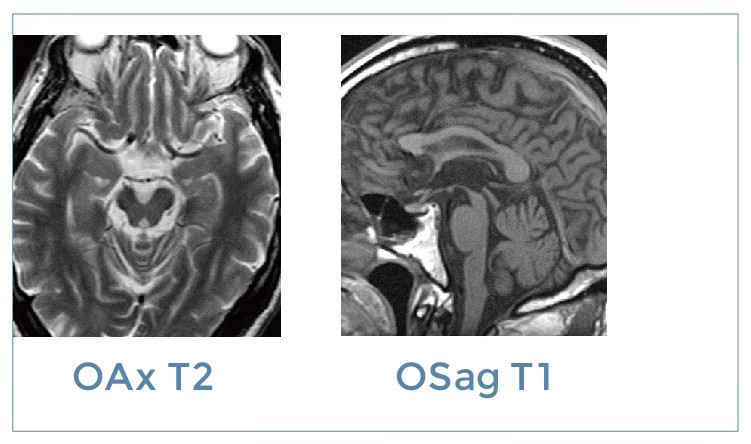

【朗润影像档案】20191115磁共振影像病例结果讨论